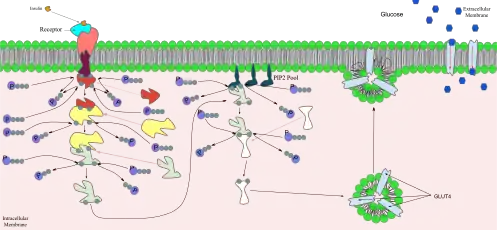

The Insulin Receptor is a type of tyrosine kinase receptor, in which the binding of an agonistic ligand triggers autophosphorylation of the tyrosine residues, with each subunit phosphorylating its partner. The addition of the phosphate groups generates a binding site for the insulin receptor substrate (IRS-1), which is subsequently activated via phosphorylation. The activated IRS-1 initiates the signal transduction pathway and binds to phosphoinositide 3-kinase (PI3K), in turn causing its activation. This then catalyses the conversion of Phosphatidylinositol 4,5-bisphosphate into Phosphatidylinositol 3,4,5-trisphosphate (PIP3). PIP3 acts as a secondary messenger and induces the activation of phosphatidylinositol dependent protein kinase, which then activates several other kinases – most notably protein kinase B, (PKB, also known as Akt). PKB triggers the translocation of glucose transporter (GLUT4) containing vesicles to the cell membrane, via the activation of SNARE proteins, to facilitate the diffusion of glucose into the cell. PKB also phosphorylates and inhibits glycogen synthase kinase, which is an enzyme that inhibits glycogen synthase. Therefore, PKB acts to start the process of glycogenesis, which ultimately reduces blood-glucose concentration.[17]

Effect of insulin on glucose uptake and metabolism. Insulin binds to its receptor (1), which, in turn, starts many protein activation cascades (2). These include: translocation of Glut-4 transporter to the plasma membrane and influx of glucose (3), glycogen synthesis (4), glycolysis (5), and fatty acid synthesis (6).

Effect of insulin on glucose uptake and metabolism. Insulin binds to its receptor (1), which, in turn, starts many protein activation cascades (2). These include: translocation of Glut-4 transporter to the plasma membrane and influx of glucose (3), glycogen synthesis (4), glycolysis (5), and fatty acid synthesis (6). Signal transduction of Insulin: At the end of the transduction process, the activated protein binds to the PIP2 proteins embedded in the membrane.

Signal transduction of Insulin: At the end of the transduction process, the activated protein binds to the PIP2 proteins embedded in the membrane.